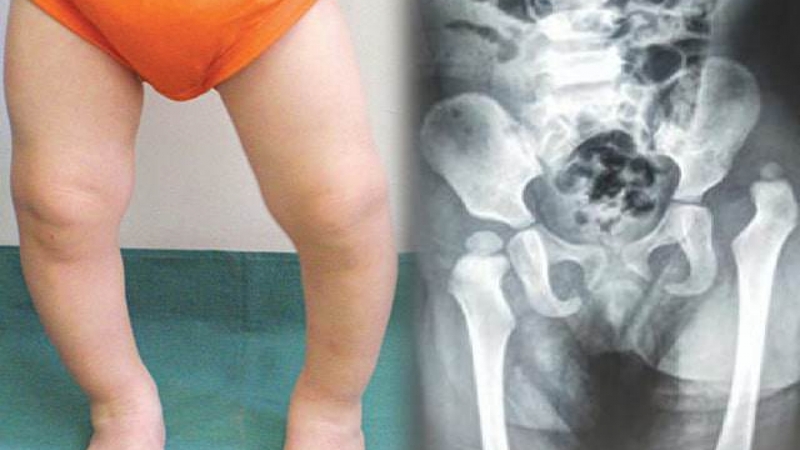

Loạn sản khớp háng tiến triển (Developmental Dysplasia of the Hip - DDH) là một tình trạng thường gặp ở trẻ sơ sinh và trẻ nhỏ khi xương đùi và bàn chân không phát triển đúng cách trong giai đoạn bào thai. Trước đây, nó được ghi nhận như trật khớp háng bẩm sinh. Đối với các em bé gặp phải tình trạng này cần thăm khám định kỳ trong suốt 1 năm đầu đời và tiếp tục theo dõi cho đến 3,5 tuổi.

Triệu chứng của loạn sản khớp háng có thể khác nhau tùy thuộc vào độ tuổi và mức độ nghiêm trọng của từng trẻ. Có 6 biểu hiện thường gặp nhất giúp nhận biết em bé có bị loạn sản khớp háng tiến triển hay không:

Đối với trẻ trên 6 tháng tuổi, có thể xuất hiện các biểu hiện như: